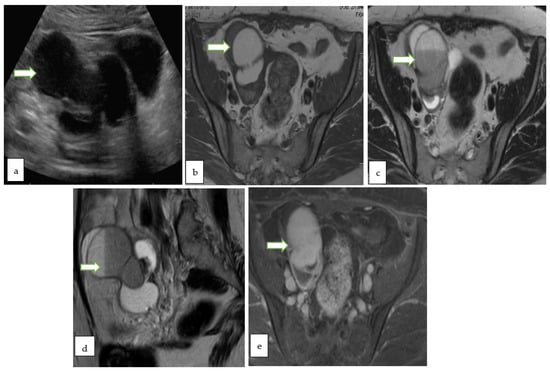

- Ultrasound is usually the primary modality to evaluate women with pelvic symptoms. It has the advantages of wide availability, feasibility, and cost-effectiveness with no radiation hazards. Limitations include operator dependence, limited field of view, and low contrast resolution